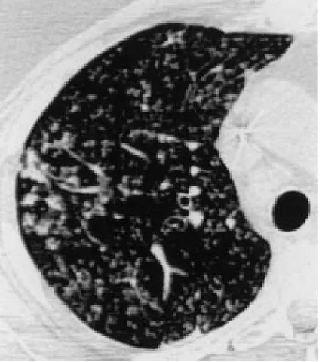

病历检查结果

2天后病理结果出来了—— 机化性肺炎